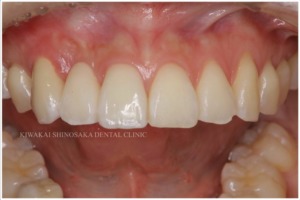

治療後

約2ヶ月後、手術箇所の生着を確認し、ジルコニアブリッジを作製、装着しました。

装着後は就寝時の歯軋りや食いしばりからブリッジを守るため、ナイトガードの使用をお願いしています。

患者さまにはその後、6ヶ月に1回の定期的なメンテナンスを受けていただいており、良好な状態を維持しています。